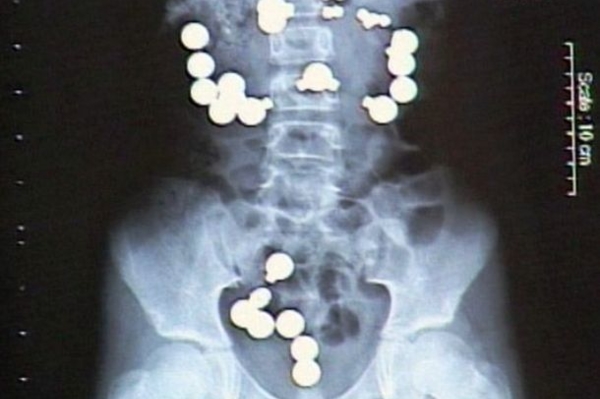

Неожиданные находки в теле человека: ТОП-20 фото

Люди порой поражают медиков странными вкусовыми пристрастиями и удивляют неожиданными вещами, которые по разным причинам оказались в человеческом теле и доступны взору только на рентгеновских снимках. Смотри подборку самых неожиданных находок в человеческом организме

Некоторые люди умудрились удивить медиков странными находками, обнаружившимися в их желудках и телах на рентгеновских снимках. Следует отметить, что многие предметы оказались в человеческом организме волей случая, но некоторые из них - по воле их носителей.